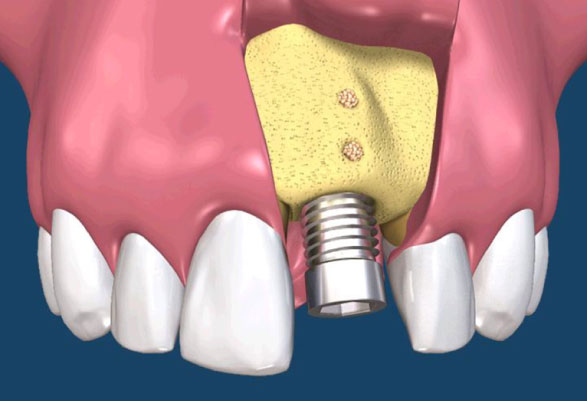

• 假牙製作階段

植體接出後,給予臨時假牙試戴,進行調整咬合與美觀部位的修飾,待病人適應一段時間後,依據調整好的咬合狀態進行印模製作永久假牙。(圖01-03)

補骨手術

植牙的患者,由於有不同的骨缺損,因此大都需要補骨牙周固定,常見術式有幾下幾種:

拔牙後的齒槽吸收往往造成植牙和膺復上的困難。骨脊保存術是一項用來在牙齒拔除時最小化齒槽吸收和最大化骨形成的術式。臨床上,保存牙齒的方法很多,包括拔牙時盡量減少對周圍齒槽骨或黏膜的傷害,使用軟或硬組織移植,或合併使用再生膜和骨移植。病患於拔牙前經過仔細的評估後,採用骨脊保存術可以減少拔牙後齒槽骨的吸收,並有效的維持齒槽的外形。(圖04-08)